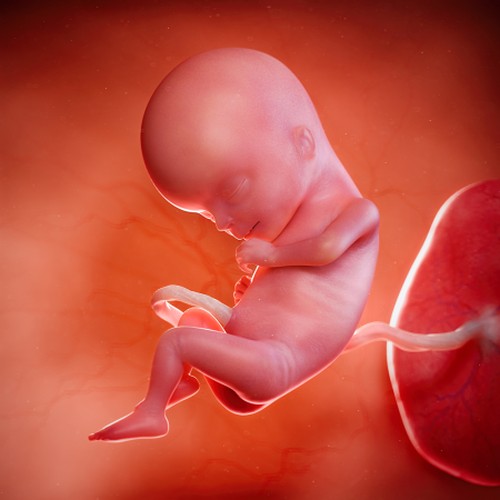

На 15-й неделе беременности размер плода составляет от 94 до 103 мм, а его вес колеблется в пределах 50-70 г. По своим габаритам он напоминает апельсин. У плода уже сформированы пропорциональные тело и голова, а его кожа представляет собой тонкий прозрачный слой, сквозь который видны кровеносные сосуды и капилляры.

На данном этапе беременности плод полностью покрыт особым пушком, защищающим восковидную смазку. Особенно густо этот пушок располагается на бровях и поверхности черепа. В коже головы начали развиваться волосяные фолликулы, которые начинают вырабатывать фермент, отвечающий за цвет волос малыша.

Что еще происходит с ребенком на 15-й неделе? Он становится очень активным: может кувыркаться в матке, где еще достаточно места, сжимать кулачки, трогать свое лицо и пуповину. Все суставы уже сформированы, поэтому он легко сгибает руки и ноги. Половину времени он проводит в состоянии сна, а вторую половину бодрствует.